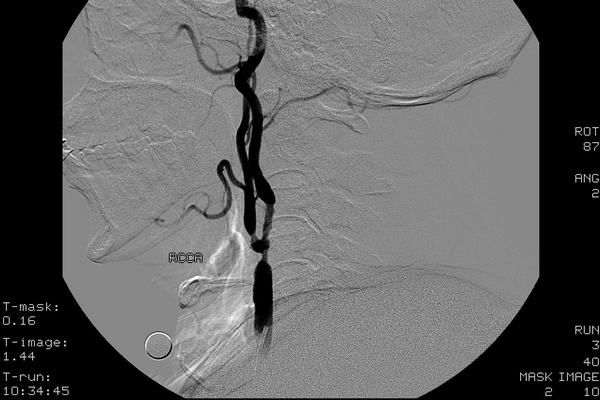

CEA手术取出的完全堵死右颈动脉分叉的斑块,这在美国几乎没有,但在中国很常见

CT——颈总动脉末端及颈内、颈外动脉起始段重度狭窄

超声——颈动脉分叉处重度狭窄